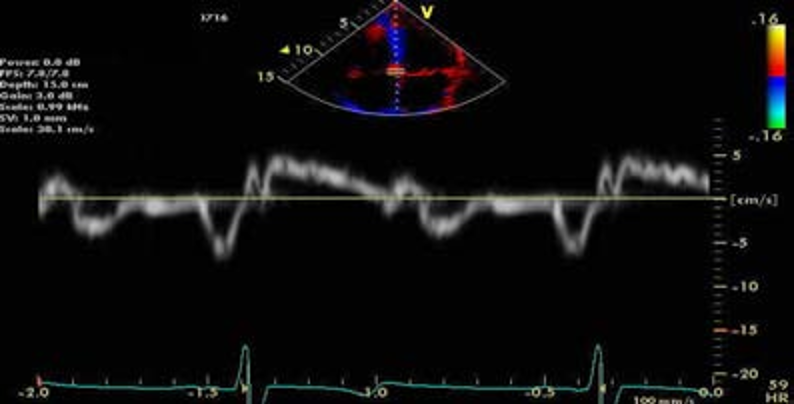

同一患者,间隔侧二尖瓣环E/e'= 80/4 = 20

同一患者,侧壁二尖瓣环E/e'= 80/5 = 16

通常室间隔e'较侧壁的e'低,室间隔的E/ e'较侧壁获得的E/ e'值偏高,基于测量位置及LVEF值不同应采用不同的界线值。

但在目前指南中,鉴于二者速度存在差异,临床中评估E/ e'时,通过测量间隔及侧壁的二尖瓣环e'并取平均值来预测左室充盈压(尤其存在局部功能障碍时必须取平均值)。

一例前间壁心肌梗塞患者的组织多普勒测量图(左为间隔侧,右为侧壁)。注意二者速度不同,应采用室间隔与侧壁e’平均值估测LV松弛性和充盈压。